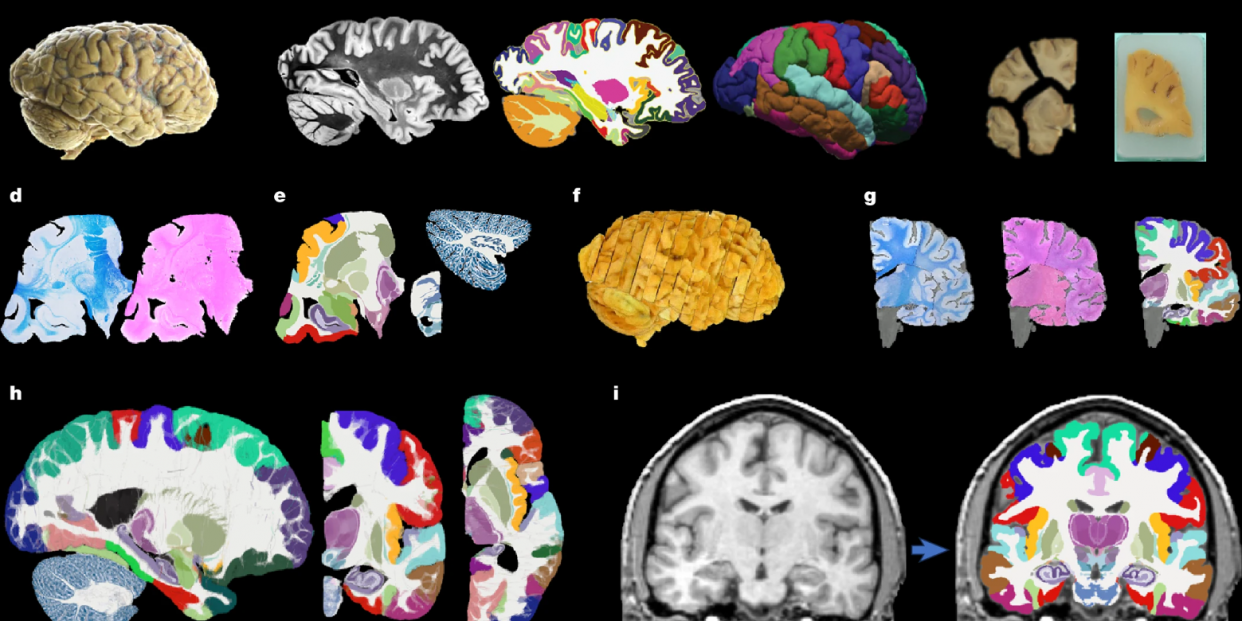

Un estudio con participación de la Universitat de Girona (UdG) ha desarrollado gracias a la inteligencia artificial (IA) el mapa "más completo y detallado" del cerebro humano hasta la fecha, que puede visualizar el cerebro humano in vivo a partir de resonancias magnéticas (RM) con alta precisión.

El atlas, de nombre NextBrain y publicado en la revista Nature, representa "un paso adelante clave" para entender y diagnosticar enfermedades neurológicas como el alzhéimer, informa la UdG en un comunicado de este jueves.

NextBrain es el resultado de 6 años de trabajo con muestras de tejido cerebral post mortem de 5 cerebros humanos, cada uno de los cuales fue diseccionado en más de 10.000 secciones microscópicas, teñidas, fotografiadas y reconstruidas digitalmente para crear un modelo 3D.

La IA permitió alinear estas imágenes con escáners MRI previos, corrigiendo distorsiones y otros artefactos provenientes de la disección asegurando una reconstrucción "precisa".

A partir de este proceso, los investigadores identificaron y etiquetaron 333 regiones cerebrales, un trabajo que sin la IA "habría requerido décadas"; el resultado es un atlas probabilístico representativo de la estructura cerebral adulta, aplicable tanto a cerebros vivos como a muestras post mortem.

El atlas, validados con miles de resonancias magnéticas de personas de distinta edad y condición, ha demostrado su capacidad para identificar automáticamente regiones cerebrales, incluidas las más pequeñas, con una precisión "similar a la de la anotación manual hecha por expertos".